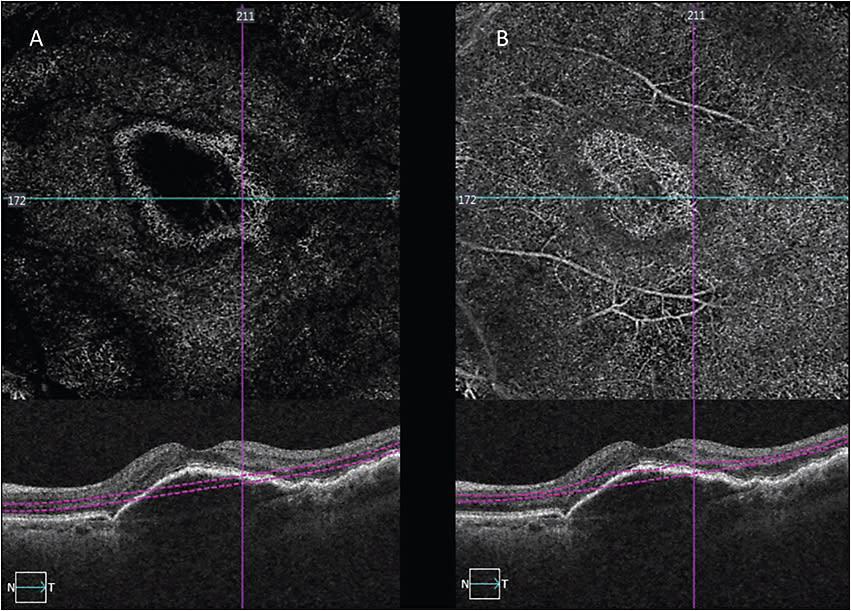

SELECT THE APPROPRIATE SCAN SIZE

The 3 mm x 3 mm scan gives better resolution than the 6 mm x 6 mm or 8 mm x 8 mm patterns (Figure 2). The higher resolution scans have in practice proven better for CNVM detection. I will let my technicians know to use the 3 mm x 3 mm scan in cases where I am looking for CNVMs. The larger scan patterns are helpful for assessing the retinal perfusion status in the superficial and deep capillary plexus in patients with DR or RVO.